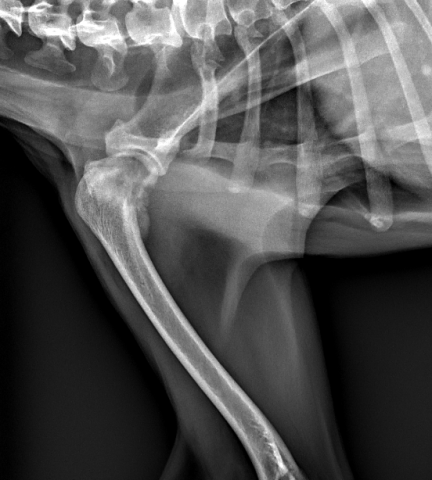

◎X線検査

痛み生じている部位をX線撮影し、まずは骨折や関節炎などの整形外科疾患の有無を確認します。骨肉腫がある程度進行してる場合は、骨融解像(骨が溶けているような所見)や骨膜反応などが認められることがあります。但し画像所見のみでは確定診断に至らないため、疑われる場合には下記の検査に進みます。

【骨肉腫 レントゲン画像】

骨肉腫 レントゲン像